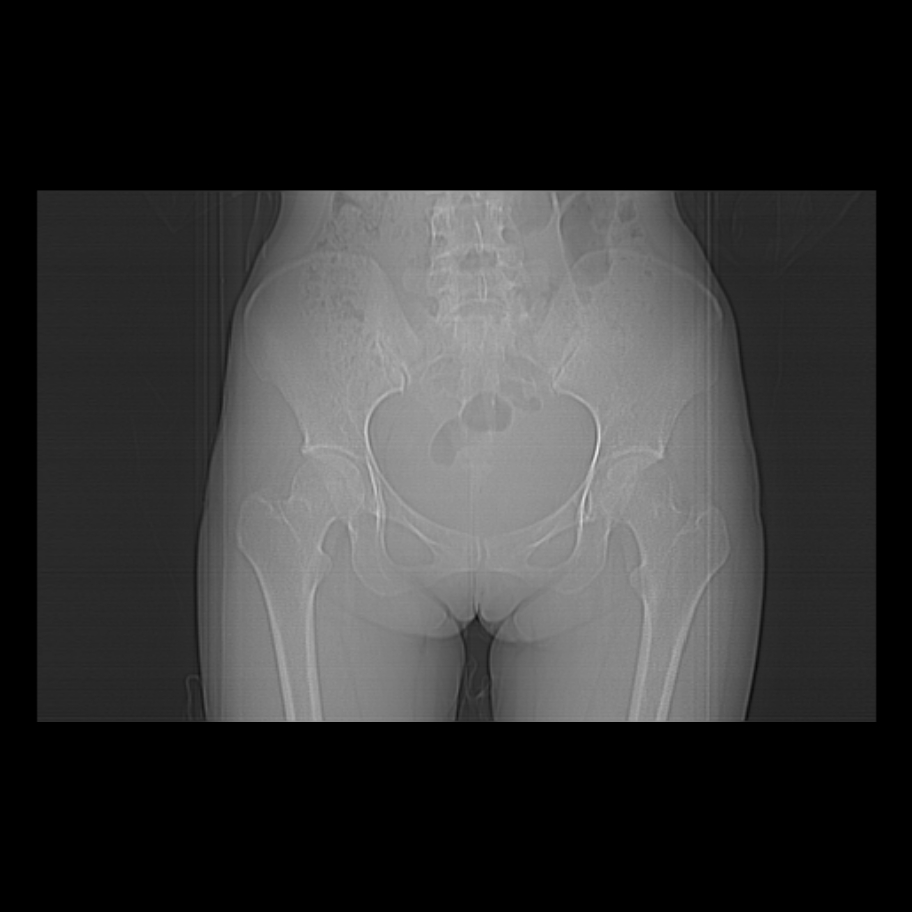

女,25岁。偶尔有右下腹不适感,余无明显异常。(结婚半年),囊壁较厚,是卵巢囊肿吗?

右侧卵巢区椭圆形囊性肿物,内壁光滑 无分隔。直肠子宫间隙内有少量积液征象。结合临床考虑卵巢巧克力囊肿,还要问问有没有痛经,本例ct怎么没有灌肠?要是灌肠或前一前口服造影剂,起码可以和肠管区别开

b超示:囊实性占位,畸胎瘤?临床有痛经。

考虑右侧卵巢囊性占位性病变(巧克力囊肿?),盆腔积液有不排除宫外孕可能,请结合临床和b超。